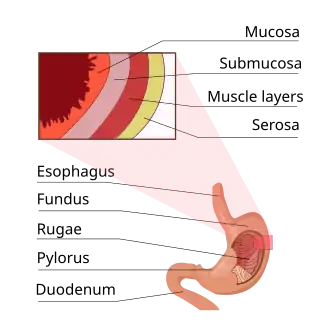

Stomach.

Stomach. -